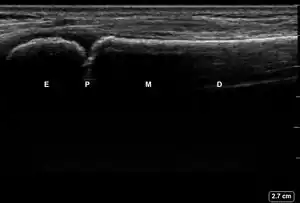

| 2 | Buckle (Torus) Fracture | "Bent" | ![]() Ultrasound dorsal view of buckle fracture of radius (shown by arrow). E = epiphysis; P = physis; M = metaphysis; D = diaphysis. | ||